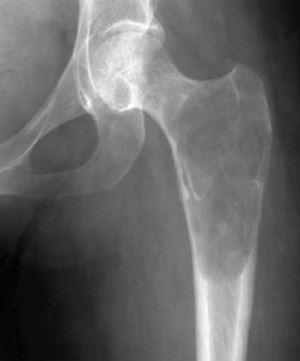

При доброкачественном типе на рентгеновском снимке видны углубления округлой формы на стенках опухоли, злокачественная характеризуется ярко выраженным остеопорозом, а литическая – гомогенным остеопорозом.

Чтобы точно определить этот тип опухоли делают ряд анализов. Рентгеновские снимки обязательны. На них видно истончение кости, которые расползается неравномерно, пораженный кортикальный слой, контуры кости вздуваются булавовидным образом и т.д.